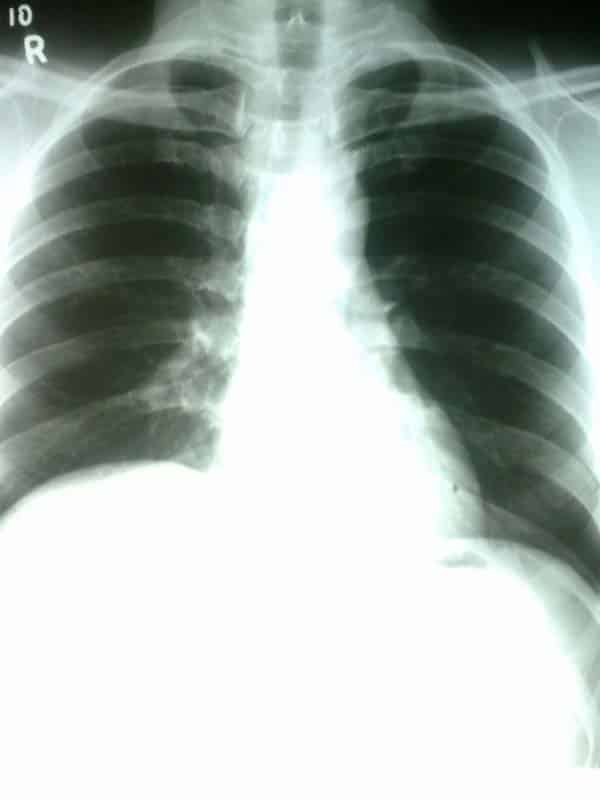

The diaphragm is a double-domed musculotendinous sheet, located at the inferior-most aspect of the rib cage. It serves two main functions: Separates the thoracic cavity from the abdominal cavity (the word diaphragm is derived from the Greek ‘diáphragma’, meaning partition). Undergoes contraction and relaxation, altering the volume of the thoracic cavity and the lungs, producing inspiration and expiration. In this article, we shall look at the anatomy of the diaphragm – its attachments, actions and associated neurovascular structures. Pro Feature - 3D Model You've Discovered a Pro Feature Access our 3D Model Library Explore, cut, dissect, annotate and manipulate our 3D models to visualise anatomy in a dynamic, interactive way. Learn More Anatomical Position and Attachments The diaphragm is located at the inferior-most aspect of the ribcage, filling the inferior thoracic aperture. It acts as the floor of the thoracic cavity and the roof of the abdominal cavity. The attachments of diaphragm can be divided into peripheral and central attachments. It has three peripheral attachments: Lumbar vertebrae and arcuate ligaments. Costal cartilages of ribs 7-10 (attach directly to ribs 11-12). Xiphoid process of the sternum. The parts of the diaphragm that arise from the vertebrae are tendinous in structure, and are known as the right and left crura: Right crus – Arises from L1-L3 and their intervertebral discs. Some fibres from the right crus surround the oesophageal opening, acting as a physiological sphincter to prevent reflux of gastric contents into the oesophagus. Left crus – Arises from L1-L2 and their intervertebral discs. The muscle fibres of the diaphragm combine to form a central tendon. This tendon ascends to fuse with the inferior surface of the fibrous pericardium. Either side of the pericardium, the diaphragm ascends to form left and right domes. At rest, the right dome lies slightly higher than the left – this is thought to be due to the presence of the liver. By TeachMeSeries Ltd (2025) Fig 1The diaphragm is split into two lobes, left and right. Note the vertebral attachments of the diaphragm are the left and right crura. Pro Feature - Dissection Images Prosection of the demonstrating the inferior surface of the diphragm. Prosection of the demonstrating the inferior surface of the diphragm. You've Discovered a Pro Feature Access our Dissection Image Library Enhance your understanding with high-resolution dissection images showcasing real-life anatomy. Learn More Pathways through the Diaphragm The diaphragm divides the thoracic and abdominal cavities. Thus, any structure that pass between the two cavities will pierce the diaphragm. There are three openings that act as conduit for these structures: Caval Hiatus (T8) Oesophageal Hiatus (T10) Aortic Hiatus (T12) Inferior vena cava Terminal branches of right phrenic nerve Oesophagus Right and left vagus nerves Oesophageal branches of left gastric artery/vein Aorta Thoracic duct Azygous vein A tip for remembering the vertebral levels: vena cava has eight letters (T8), oesophagus has ten letters (T10), and aortic hiatus has twelve letters (T12). By TeachMeSeries Ltd (2025) Fig 2View of the inferior surface of the diaphragm. Note the three openings. Actions The diaphragm is the primary muscle of respiration. During inspiration, it contracts and flattens, increasing the vertical diameter of the thoracic cavity. This produces lung expansion, and air is drawn in. During expiration, the diaphragm passively relaxes and returns to its original dome shape. This reduces the volume of the thoracic cavity. Innervation and Vasculature The halves of the diaphragm receive motor innervation from the phrenic nerve. The left half of the diaphragm (known as a hemidiaphragm) is innervated by the left phrenic nerve, and vice versa. Each phrenic nerve is formed in the neck within the cervical plexus and contains fibres from spinal roots C3-C5. The majority of the arterial supply to the diaphragm is delivered via the inferior phrenic arteries, which arise directly from the abdominal aorta. The remaining supply is from the superior phrenic, pericardiacophrenic, and musculophrenic arteries. The draining veins follow the aforementioned arteries. By TeachMeSeries Ltd (2025) Fig 3The anatomical course of the phrenic nerves, which innervate the diaphragm. Clinical Relevance Paralysis of the Diaphragm Diaphragmatic paralysis is due to an interruption in its nervous supply. This can occur in the phrenic nerve, cervical spinal cord, or the brainstem. It is most often due to a lesion of the phrenic nerve: Mechanical trauma: ligation or damage to the nerve during surgery. Compression: due to a tumour within the chest cavity. Myopathies: such as myasthenia gravis. Neuropathies: such diabetic neuropathy. Paralysis of the diaphragm produces a paradoxical movement. The affected side of the diaphragm moves upwards during inspiration, and downwards during expiration. A unilateral diaphragmatic paralysis is usually asymptomatic and is most often an incidental finding on x-ray. If both sides are paralysed, the patient may experience poor exercise tolerance, orthopnoea and fatigue. Lung function tests will show a restrictive deficit. Management of diaphragmatic paralysis is two-fold. Firstly, the underlying cause must be identified and treated. The second part of treatment deals with symptomatic relief. This is usually via non-invasive ventilation, such as a CPAP (continuous positive airway pressure) machine. By Ratnayake et al [CC BY 2.0] via BioMed Central Ltd Fig 4Chest x-ray, showing paralysis of the right hemidiaphragm. Do you think you’re ready? Take the quiz below Pro Feature - Quiz The Diaphragm Question 1 of 3 Submitting... Skip Next Rate question: You scored 0% Skipped: 0/3 1800 More Questions Available Upgrade to TeachMeAnatomy Pro Challenge yourself with over 1800 multiple-choice questions to reinforce learning Learn More Rate This Article